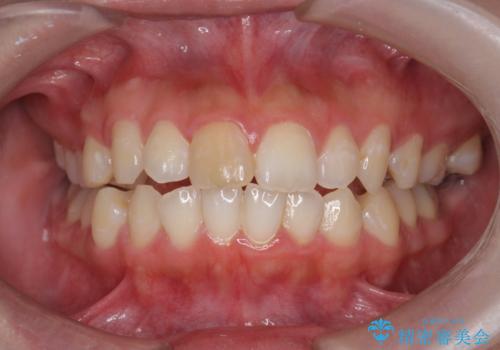

- 前歯の変色が気になる、見た目を改善したい!と審美性の回復を希望され来院されました。

ホワイトニングでは、周囲の歯との色調になじむほどには白くできないため、ジルコニアセラミッククラウンを用いて審美性を回復します。